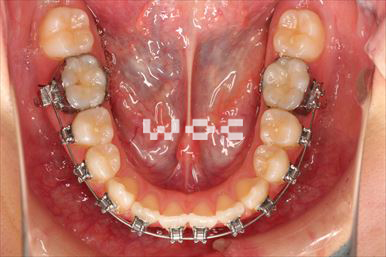

治療中1

治療中2

治療中3

治療中4

治療中5